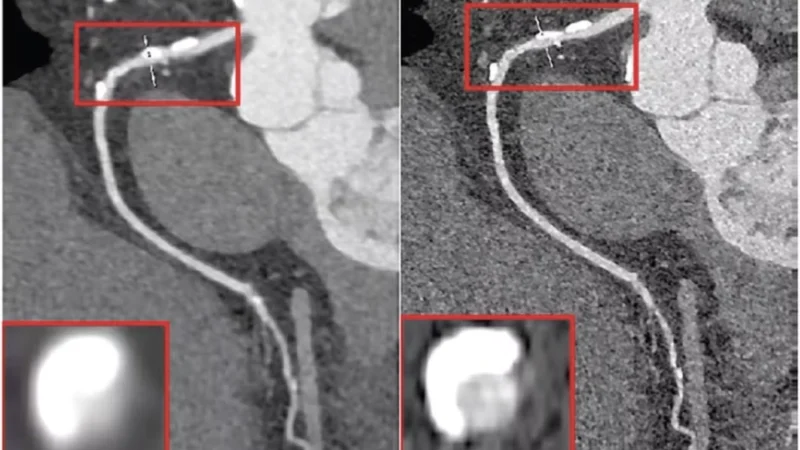

3. Spatial Resolution Advances

This improvement particularly benefits:

- Coronary stent evaluation

- Temporal bone imaging

- Musculoskeletal micro-architecture assessment

- Lung nodule characterization

Clinical PCCT systems achieve pixel sizes of 250 micrometers in standard mode10 and 150 micrometers in ultra-high-resolution mode8,9 compared to conventional CT’s typical 240-500 micrometer resolution.